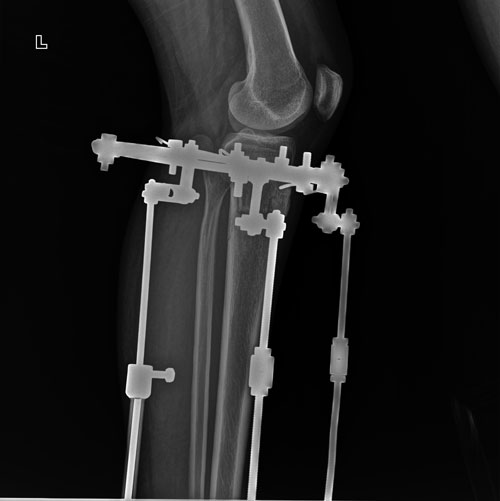

Рентген перед снятием аппаратов.

Вложения

IMG-20180827-WA0008.jpg

IMG-20180827-WA0007.jpg